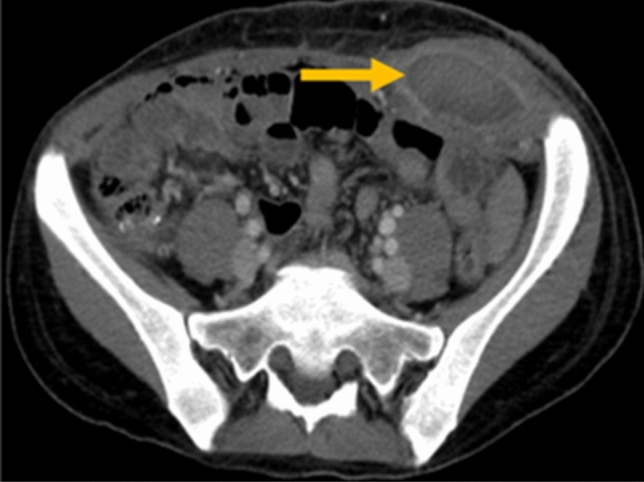

Case Report: A 43-yer-old female presented with lower abdominal pain for 2 days associated with nausea and fever. She was diagnosed with acute appendicitis and was taken for laparoscopic appendectomy. Access to the abdomen was achieved using a Veress needle at the left upper quadrant. A supraumbilical midline incision was made and a 10-mm optical trocar was inserted into the abdomen. Subsequently, two 5-mm bladed trocars were inserted in the left lower quadrant and suprapubic region. The rest of the procedure was carried out in a routine fashion. Notably, the trocars were removed under direct visualization and with no apparent bleeding from the port sites. A few hours later, a 10 × 15-cm swelling was found over the lateral abdominal wall port site associated with skin ecchymosis. The swelling was asymptomatic and the patient was discharged the next day. She presented to the emergency room 10 days later with pain associated with swelling and fever. CT imaging confirmed an abscess collection associated with the hematoma which was percutaneously drained. The patient was discharged 3 days later after removal of the drain

Discussion: The reported rate of vascular injury is about 1 to 6 per 1000 laparoscopic surgeries. Abdominal wall vessels, most commonly the inferior epigastric artery, or intraabdominal mesenteric or larger vessels may be injured. Bleeding is rarely observed during surgery as the insufflated abdomen creates a tamponade effect over the vessel. A hematoma, as seen in our case, develops in the recovery room or up to 2–3 days postoperatively. Bladed cutting trocars are more likely to cause vascular injury than smooth trocars. Abdominal wall hematomas may be managed conservatively unless causing hemodynamic instability. Mortality associated with intraabdominal injury is about 15%. Knowledge of the abdominal wall anatomy, transilluminating the abdominal wall before introducing trocars, and entering the abdomen at the correct angle decrease the possibility of vascular injury.

Figure Rule of 2/3rd. Medial 2/3rd of the abdominal wall is unsafe for trocar insertion except of avascular midline.